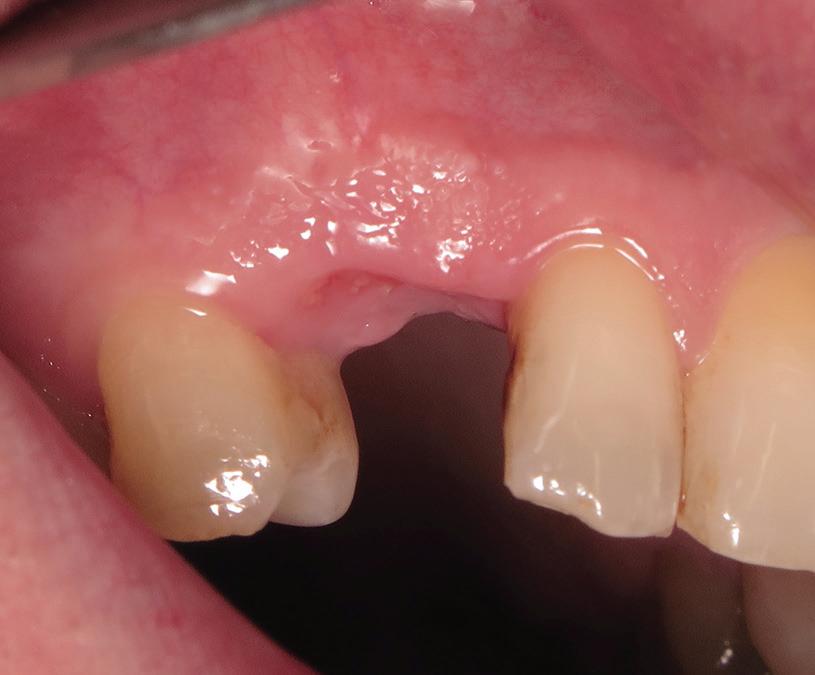

After antiseptic procedures, the surgical site is evaluated. In Fig 4, the site shows good hard and soft tissue volume consistent with that seen in the preoperative planning scans.

Fig 4. The fully healed site is ready for implant placement.